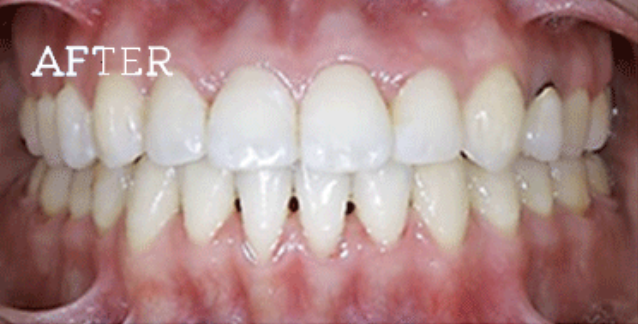

症例

お困りごとを参考に、治療のbefore・afterが確認できます。治療過程や期間、費用などを参考にご覧ください。